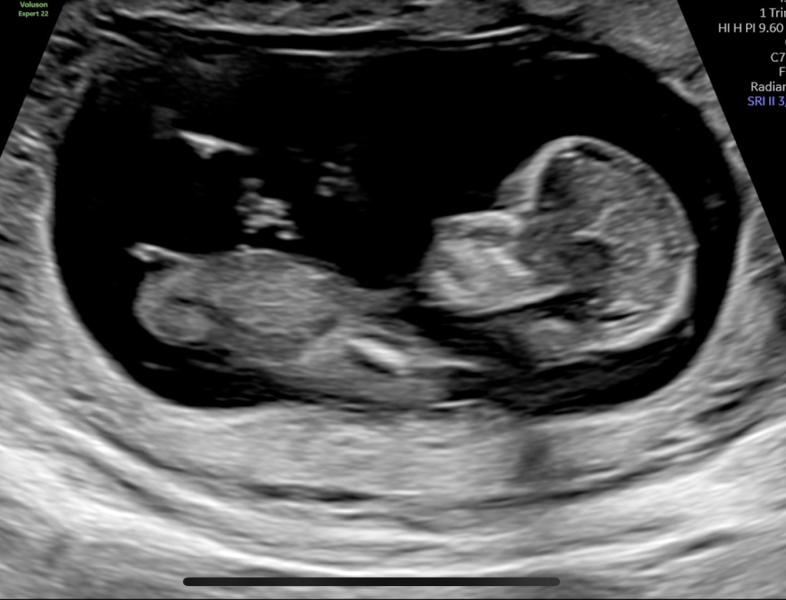

Вот такой у меня пузожитель ☺️

В 12 недель предположили по половому бугорку, что будет девочка 👧

Есть тут знатоки? 😊